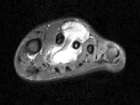

21 year old male with swelling and pain in left foot for six months

Zoom image: Radiological image Radiological image.